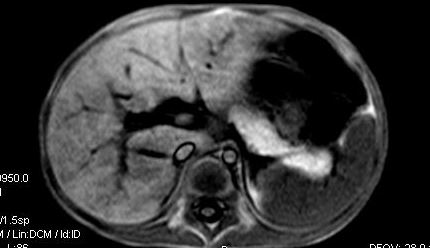

标题: V0176(MRI):小儿发热,肝脾大,肝内病变 [打印本页]

标题: V0176(MRI):小儿发热,肝脾大,肝内病变

5岁,2006年8月曾行阑尾炎手术,现发热半年